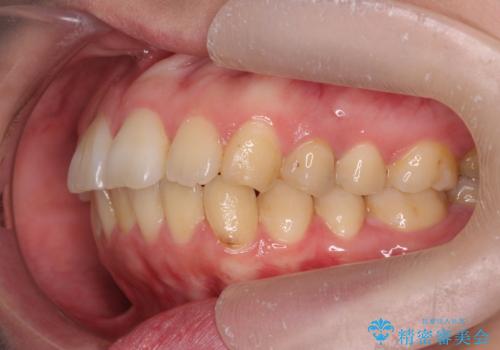

歯を抜かずに行う前歯の角度の改善

- 歯を抜かずに前歯の角度を改善したい、と矯正治療を希望され来院されました。

可及的に前歯部にIPR(歯間の削合)を行い、抜歯をせずマウスピース矯正システムインビザラインで歯の排列を行っていく治療計画としました。

治療の前後を比べると、がたつきや歯の角度が改善したことがしっかりと確認されました。